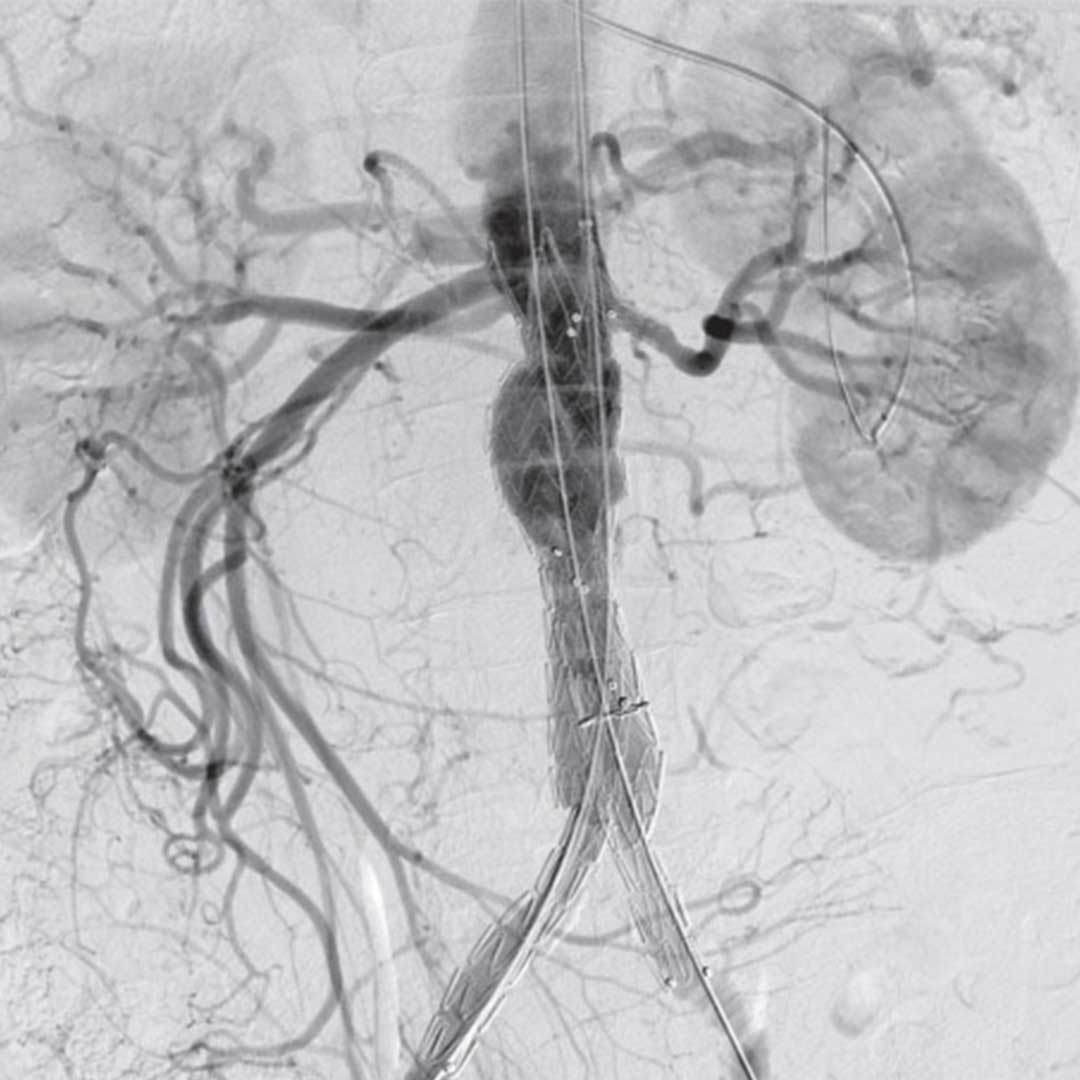

What a fantastic image! Interventional and endovascular procedures are revolutionising the field of surgery. It is fascinating to see the anatomy light up like this, and even more incredible to be able to ‘intervene’ with minimally invasive procedures. EVAR is now widely accepted as the gold standard of care for most vascular procedures. It is incredible watching them at work and watching those stents be deployed in real time!

Video Ref: https://www.youtube.com/watch?v=Igy4mpl5NQI